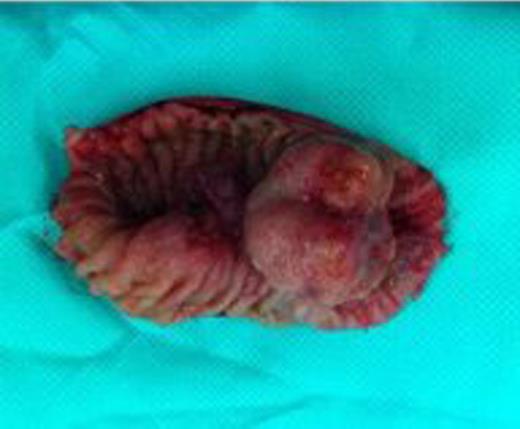

A laparotomy was performed with small bowel resection around the intussusception and primary anastomosis (Fig. 3). The excised segment included a 4-cm lesion (Fig. 4). The excised lesion was composed of areas of spindle and epithelioid cells, and immunohistochemical analysis showed positive staining with CD117, DOG1 and SMA: attributes restricted in the gut to the interstitial cells of Cajal. Genetic analysis detected an exon 11 mutation.